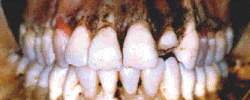

Imagem da arcada dentária obtida em inclinação similar à

fotografia a ser confrontada. Posicionamento realizado por intermédio do Craniostato LAF

IML DF, auxiliado pelo sistema de superposição computadorizada em tempo real LAF IML DF |

Comparação do odontograma da ossada e da pessoa

desaparecida. A simples comparação das restaurações não resultariam uma

identificação positiva absoluta em função da alta freqüência das mesmas em nossa

população. Portanto, o prontuário odontológico deve, na medida do possível, incluir

fotografias das arcadas dentárias. |